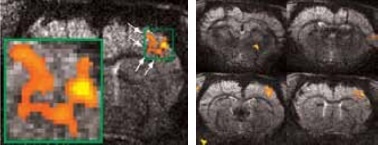

Matrices up to 256 x 256 were obtained with a four-element array coil, resulting in 75 x 75 x 1000 μm3 resolution. The activation becomes more resolved at this high resolution and allows the detection of sub-structures and shape in thalamus areas S1 and S2, as shown in Figure 3.

Figure 3. High resolution BOLD activation at 11.7 Tesla using the four-element array coil with a resolution of 75 x 75 x 1000 μm3 for detection of (left) sub-structures within S1, and activation within other regions along the neuronal pathway: S2 and thalamus. Image Credit: Bruker BioSpin Group